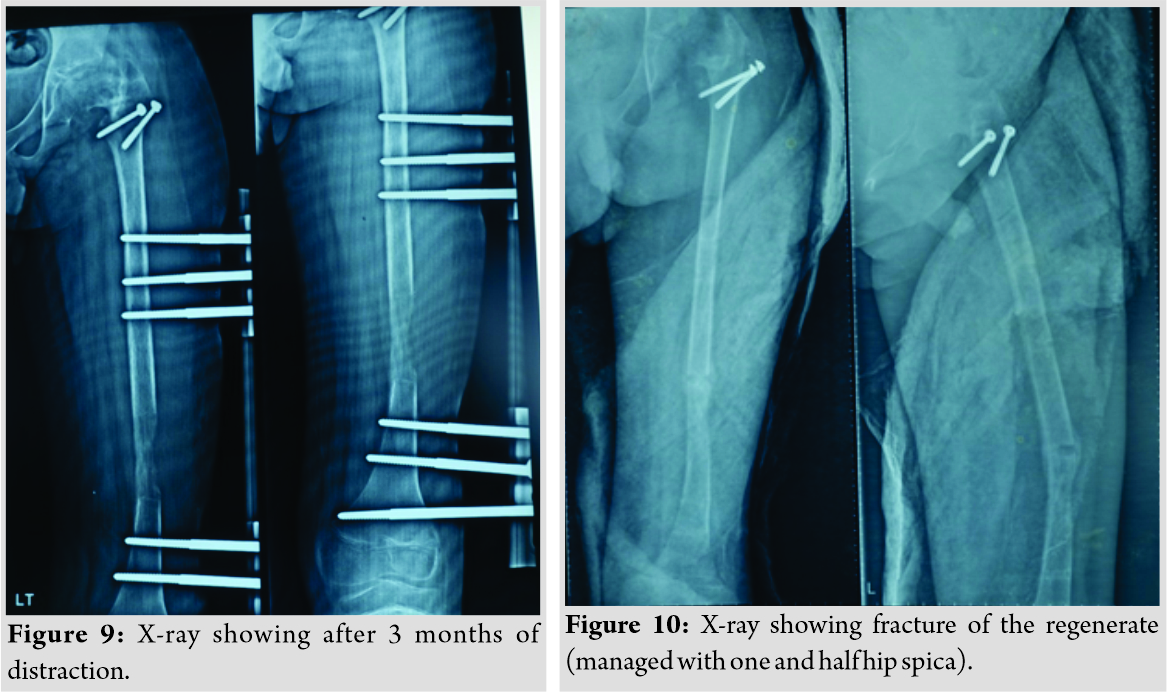

The second patient, a 14-year-old male, presented to us with complaints of limping in the left lower limb without any pain in the hip joint. He also had a history of septic arthritis in the left hip which was managed non-operatively in a village hospital. There was no history of trauma, weight loss, or tuberculosis. On examination, it was found that the patient had limited terminal hip ROM with severe restriction in hip abduction (25°). There was a true shortening of 6 cm in the left femur and the patient walked with abductor lurch without any ankle equinus with excessive flexion in the opposite knee. An X-ray revealed severe coxa vara on the left side with increased acetabular index (Fig. 7). There was minimal joint space narrowing medially. The femoral diaphysis was thin as compared to the opposite side. The power of the muscles around the hip and knee was comparable to the opposite side. Based on these findings, it was classified as a case of Choi’s Type 2 septic sequelae of the hip with 6 cm of femoral shortening. The patient underwent trochanteric advancement distally as described in the previous case along with a simultaneous application of monorail external fixator and corticotomy in the distal femur. The distraction started on the 5th post-operative day in equal increments of 0.25 mm every 6 hourly (Fig. 8 and 9). After achievement of limb length equalization, the fixator was removed after 114 days. Three weeks after this, the patient presented with a fracture of the regenerate with minimal angulation and was managed further by one and a half spica cast for further 4 weeks (Fig. 10). At latest 12 months follow-up, the patient was walking normally with minimal abductor lurch.

The treatment of sequelae of the septic hip depends on the stability of the hip joint, the desire of the patient for a mobile hip and limb length. Surgical options vary from pelvic support osteotomy to modified Albee hip arthroplasty to IHR to arthrodesis and hip arthroplasty [1]. Unstable hip with positive telescopy sign is usually treated by pelvic support osteotomy where an osteotomy is done in the proximal femur at the level of ischial tuberosity so that the lesser trochanter sits into the residual acetabulum creating a stable hip [5]. The problem with this procedure is, it places the extremity in valgus alignment with a deviation of the mechanical axis of the limb. To address this problem, Ilizarov developed a procedure where two-level osteotomy is done, one at the proximal femur and one distal so that mechanical axis of the limb is aligned simultaneously with the equalization of limb length. Various authors have reported good to excellent results with this technique and are summarized in Table 2. IHR is a technically demanding procedure with requirement of two-level corticotomy, one proximally for lengthening and second distally for aligning the limb parallel to the opposite side. Furthermore, in our experience, the acceptability of Ilizarov to the patient is poorer than the monorail fixator. Another factor is cost, which is more in Ilizarov ring fixator. In view of all this issues, we opted for monorail fixator. There are various procedures described in the literature for the management of patients with a stable hip. Most of these studies have concentrated on femoral lengthening only with various techniques such as Ilizarov or lengthening over an intramedullary nail [3, 5]. In our experience, in the management of infantile septic hip sequelae, Choi Type 2 with femoral shortening is a relatively uncommon condition. To address this problem, one must concentrate not only on achieving limb equalization but also reduction of abductor lurch. The later can very well be taken care of by distalization of GT with care taken not to injure the abductors. In both of our cases, it was addressed and at the end of 12 months follow-up, the children were having a mobile hip, equalized limb length, and minimal abductor lurch. We had a complication of fracture of the regenerate and are a well-known complication as reported in the literature [6, 7]. To address this complication, we recommend that the fixator must be kept on the limb for the same time it was kept for distraction. One should not worry too much if a fracture of the regenerate occurs as this can be managed easily by POP cast application for further 4–6 weeks.